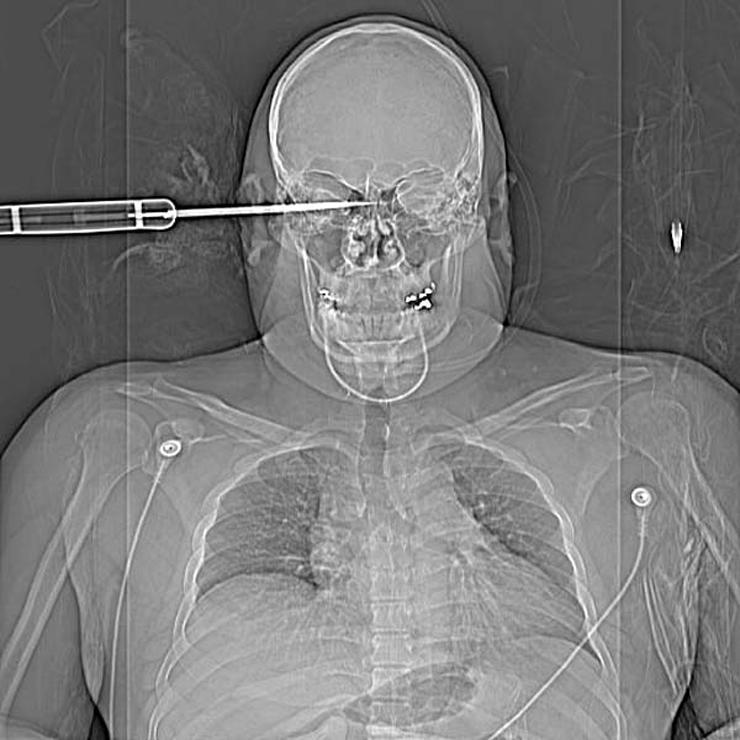

Сверло

18-дюймовое сверло пронзило глаз человека.